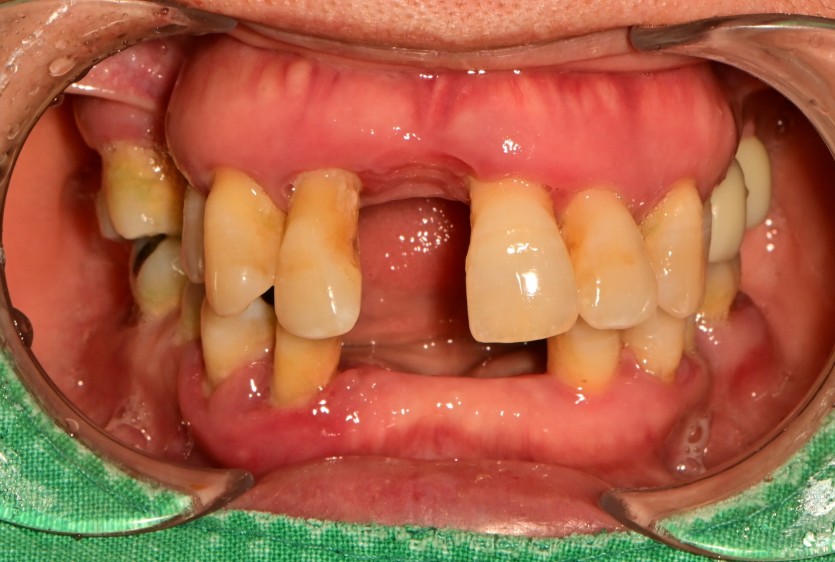

만 56세 상 하악 임플란트 증례

상 하악 임플란트 증례입니다.

12개의 임플란트로 완성하였습니다.

(상악 6개, 하악 6개)